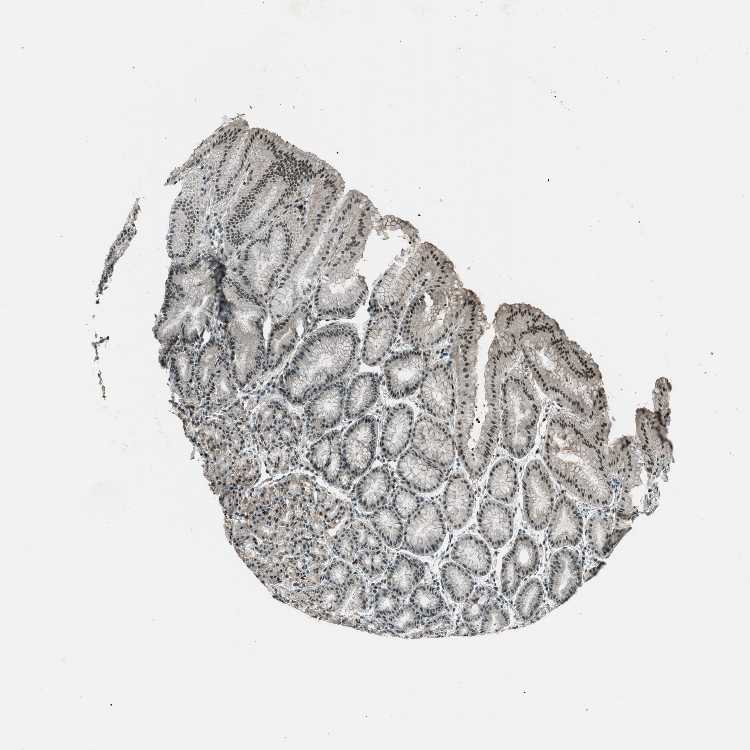

STOMACH 2 - Antibody stainingi

Antibody staining in the annotated cell types in the current human tissue is reported as not detected, low, medium, or high, based on conventional immunohistochemistry profiling in selected tissues. This score is based on the combination of the staining intensity and fraction of stained cells.

Each image is clickable and will lead to virtual microscopy that enables deeper exploration of all samples and also displays staining intensity scores, fraction scores and subcellular localization as well as patient and tissue information for each sample.

Antibody HPA017284Antibody CAB003703

Glandular cells HighHigh